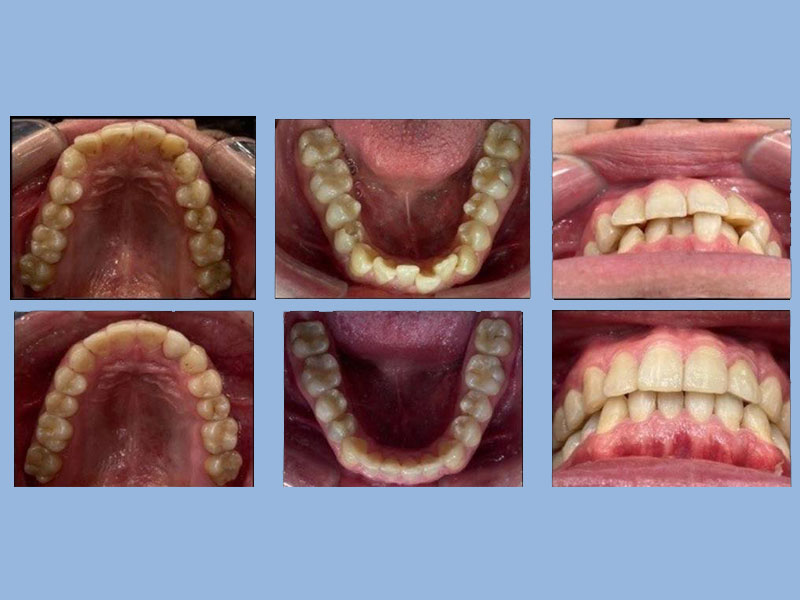

彭小姐 (24歲) 矯正完成

狀態 : 牙齒擠、沒拔牙、中線不正